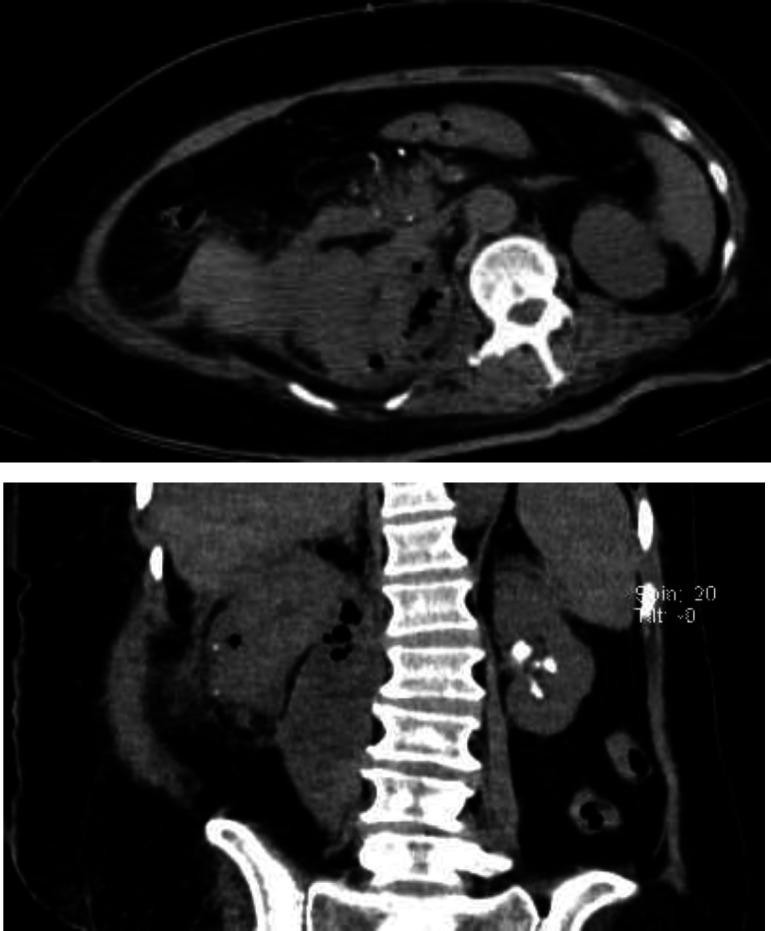

A 55-year-old female presented with a history of type 2 diabetes mellitus, and a stroke leading to a left-sided hemiplegia state for 7 years, coronary artery bypass grafting(CABG), hypertension(HTN) , seizure, progressive fatigue, loss of appetite , fecal and urinary incontinence and right costovertebral angle tenderness. According to clinical signs, symptoms and documentation of gas within the renal parenchyma on computed tomography (CT) of abdomen, of EPN diagnosis was suggested; however histopathologic evaluation showed acute emphysematous pyelonephritis on chronic xanthogranulomatous pyelonephritis.

一名55岁女性,有2型糖尿病病史,因中风导致左侧偏瘫状态7年,曾接受冠状动脉搭桥术(CABG)、患有高血压(HTN)、癫痫,出现进行性疲劳、食欲不振、大小便失禁以及右肋脊角压痛。根据临床体征、症状以及腹部计算机断层扫描(CT)显示肾实质内有气体,提示为EPN诊断;然而组织病理学评估显示为慢性黄色肉芽肿性肾盂肾炎合并急性气肿性肾盂肾炎。